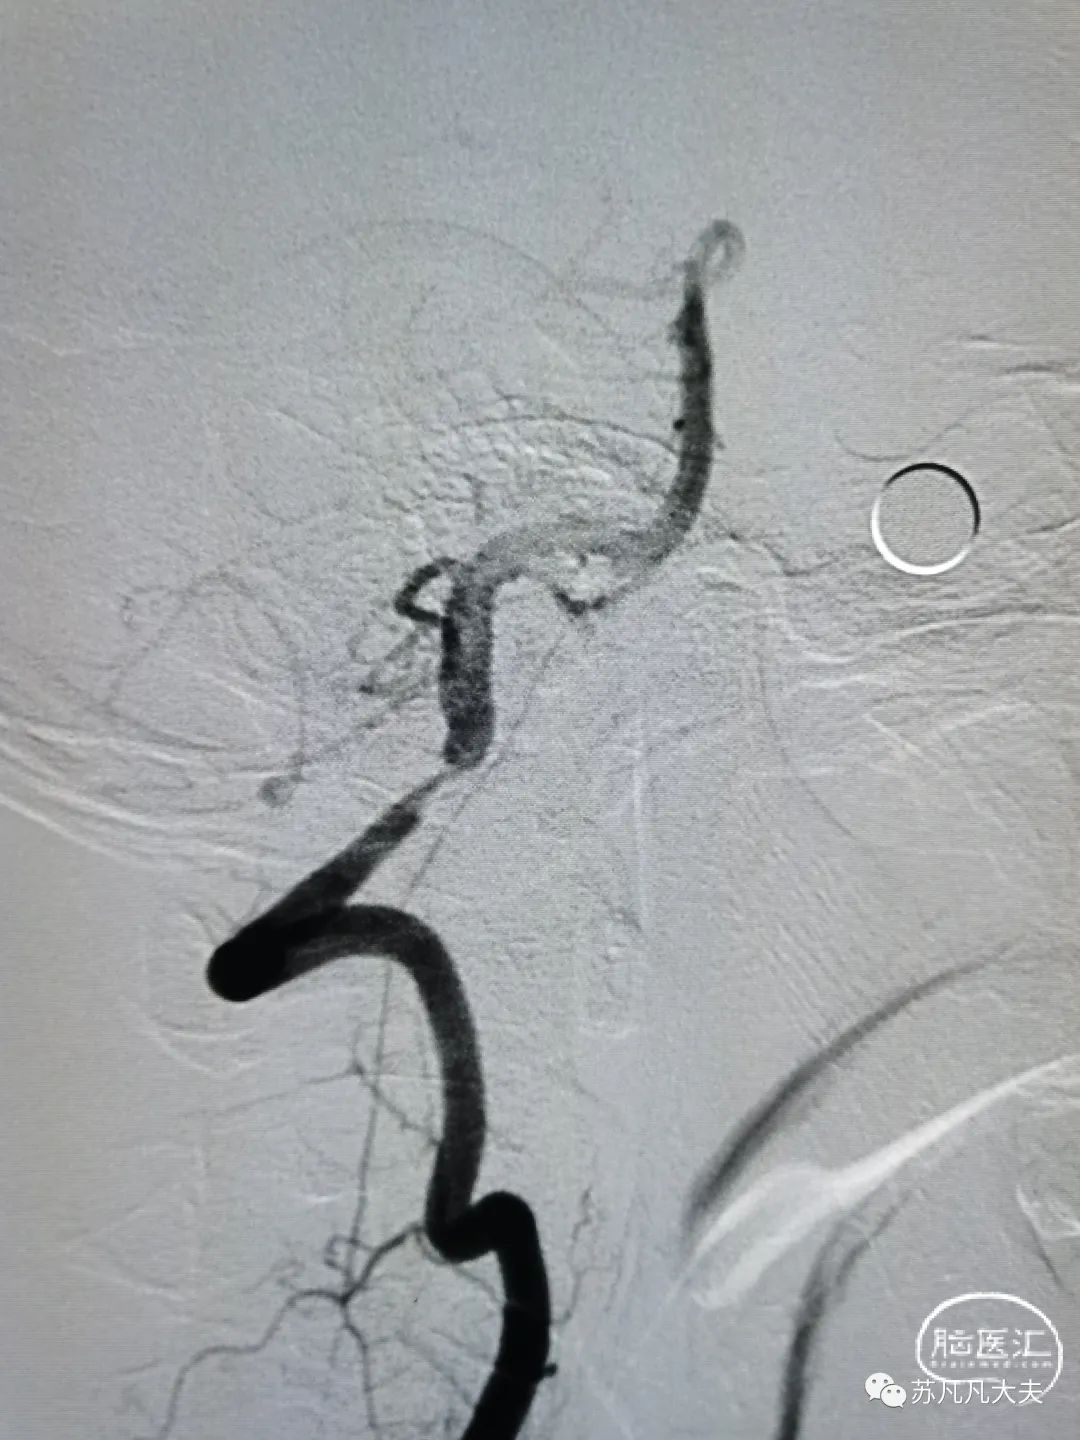

2.5/15球囊预扩后仍残余重度狭窄

4.5/13颅内支架定位,6atm释放

支架后颅内段狭窄解除